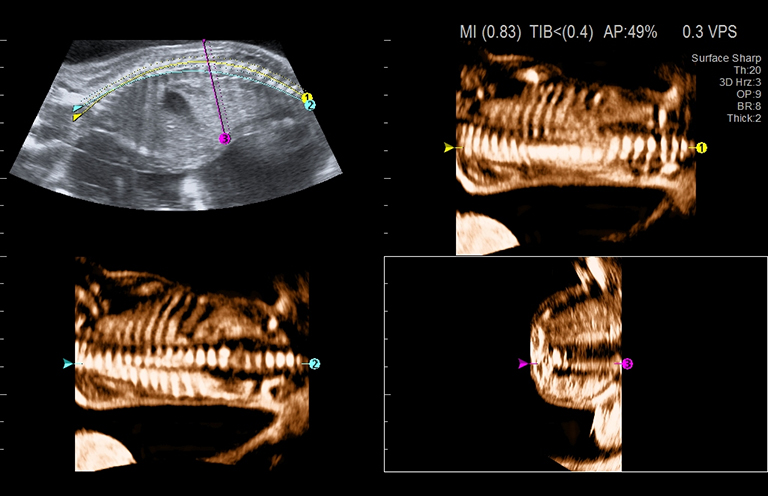

Aplicación: Obstetricia

Función/análisis: MPR curvo

Comentarios: Feto (19 semanas)